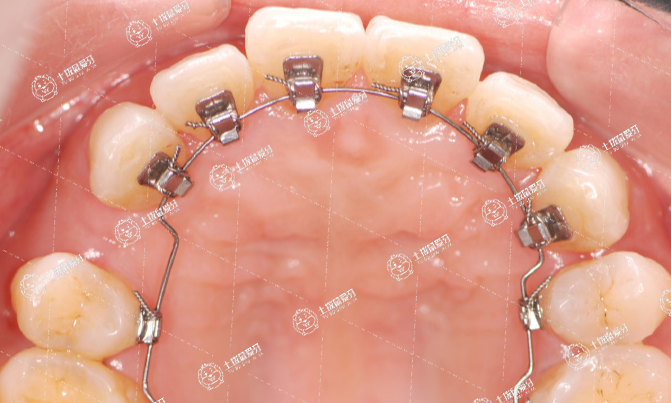

人們對(duì)隱形矯治器的探索從未停步,舌側(cè)托槽矯正技術(shù)應(yīng)運(yùn)而生。它是將托槽等裝置粘貼在內(nèi)側(cè)的一種牙齒矯治方式。

由于舌側(cè)正畸的矯治器全部安裝于牙齒的舌側(cè)面進(jìn)行正畸治療,因此旁人完全看不見托槽鋼絲,達(dá)到“隱形”矯治的效果。

舌側(cè)正畸技術(shù)操作難度大,對(duì)正畸醫(yī)生的技術(shù)要求非常高,因此它所需的矯治費(fèi)會(huì)比較高。

此外,剛戴上舌側(cè)托槽矯治器時(shí)患者的舒適度較差,對(duì)說(shuō)話發(fā)音有一定影響(一段時(shí)間后即可適應(yīng))。